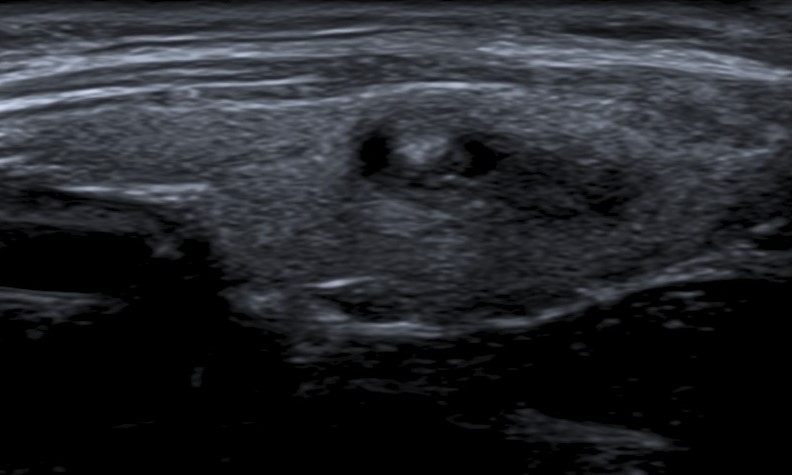

Márgenes

Es el borde entre el nódulo y el parénquima tiroideo adyacente o las estructuras extratiroideas. Se clasifican en “lisos” (Fig. 4) cuando son bien definidos, curvilíneos, de forma esférica o elíptica y no presentan interrupción en su extensión; “irregulares” (Fig. 5) cuando son espiculados o dentados, y puede dibujarse todo el contorno, lo que los diferencia de los “mal definidos” (Fig. 6), en los cuales es difícil distinguir adecuadamente del parénquima tiroideo. Se denominan “lobulados” (Fig. 7) cuando presentan protrusiones redondeadas y de diferentes tamaños. El “halo” (Fig. 8) es un anillo hipoecoico que rodea al nódulo, y puede rodearlo en forma parcial o completa. Este se considera una cápsula fibrosa que se observa más comúnmente en nódulos benignos, aunque también puede estar presente en algunos nódulos malignos2,18. En la literatura publicada, la mayoría de los autores mencionan que el tipo de márgenes que más frecuentemente se asocia a malignidad son los irregulares1,2,12,15,19,20,21,22, mientras que otros autores indican a los mal definidos16,23) como característica de malignidad.